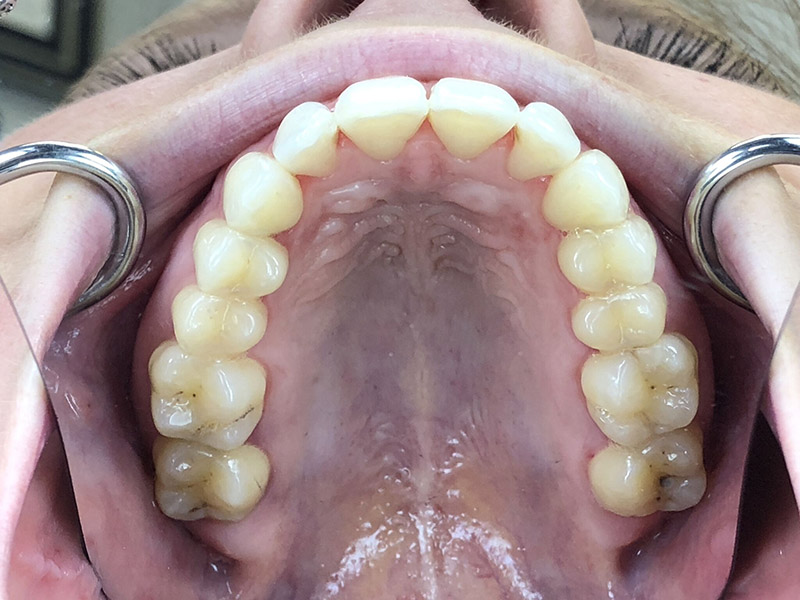

On peut constater ici :

• Une série de 8 aligneurs supplémentaires à changer toutes les semaines cette fois-ci

• Un ajout de 2 RIP au maxillaire pour le décalage des milieux

• Un ajout de 3 RIP à la mandibule pour le décalage des milieux

• Un nombre de taquets très inférieur au premier Clincheck, les mouvements à faire étant bien moins importants au final

La contention finale se fera par gouttières amovibles nocturnes bimaxillaires.

Comme on peut le constater, la durée du traitement n’aura pas excédé 10 mois au final, avec deux séries de gouttières, et un stripping relativement peu invasif pour que la patiente soit satisfaite du résultat. En ajoutant un blanchiment en ambulatoire, les dents ont retrouvé un aspect éclatant.